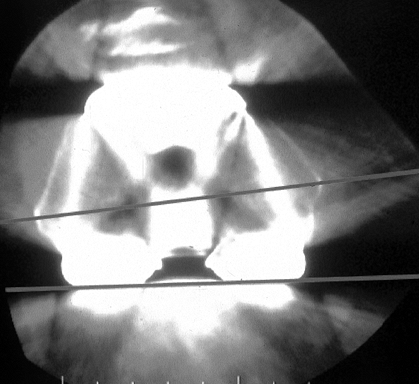

Figure 109.1. A:

Patellofemoral radiograph of patient who presented with symptoms of “giving way.” Reconstruction of medial collateral ligament was performed by her surgeon, but in fact the buckling was caused by patellar dislocation. B: Intraoperative photograph showing that the patella tracks directly over the lateral femoral condyle. The patellar tracking problem resulted from malrotation of the femoral and tibial components. |

malrotation of either the tibial or femoral components (Fig. 109.1B).